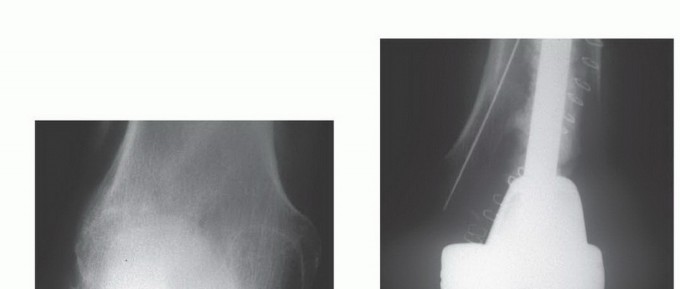

يُعد العلاج بالتبريد، خاصةً بتقنية الصب المباشر بالنيتروجين السائل، ثورة حقيقية في علاج أورام العظام، حيث يقدم بديلاً فعالاً وآمنًا للجراحات الكبرى، مع الحفاظ على الطرف المصاب ووظيفته. يعتمد هذا النهج على تدمير الخلايا السرطانية عن طريق تعريضها لدرجات حرارة منخفضة جدًا، مما يؤدي إلى تجميدها وموتها.

آلية عمل العلاج بالتبريد

تتمثل الفكرة الأساسية في تجميد الخلايا السرطانية وتذويبها بشكل متكرر. عند تجميد الخلايا، تتكون بلورات الثلج داخل وخارج الخلايا، مما يؤدي إلى:

* تمزق أغشية الخلايا: بلورات الثلج الحادة تمزق الجدران الخلوية.

* تلف العضيات الداخلية: تدمير الميتوكونندريا وغيرها من العضيات الحيوية.

* خلل في التوازن الكيميائي: اضطراب في تركيز الأملاح داخل وخارج الخلية.

* انسداد الأوعية الدموية: تدمير الأوعية الدموية الدقيقة التي تغذي الورم، مما يؤدي إلى نقص الأكسجين والمغذيات وموت الخلايا.

* الاستجابة المناعية: قد يحفز العلاج بالتبريد استجابة مناعية ضد الخلايا السرطانية المتبقية.